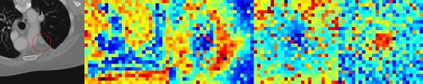

Evaluating lesion progression and treatment response via longitudinal lesion tracking plays a critical role in clinical practice. Automated approaches for this task are motivated by prohibitive labor costs and time consumption when lesion matching is done manually. Previous methods typically lack the integration of local and global information. In this work, we propose a transformer-based approach, termed Transformer Lesion Tracker (TLT). Specifically, we design a Cross Attention-based Transformer (CAT) to capture and combine both global and local information to enhance feature extraction. We also develop a Registration-based Anatomical Attention Module (RAAM) to introduce anatomical information to CAT so that it can focus on useful feature knowledge. A Sparse Selection Strategy (SSS) is presented for selecting features and reducing memory footprint in Transformer training. In addition, we use a global regression to further improve model performance. We conduct experiments on a public dataset to show the superiority of our method and find that our model performance has improved the average Euclidean center error by at least 14.3% (6mm vs. 7mm) compared with the state-of-the-art (SOTA). Code is available at https://github.com/TangWen920812/TLT.